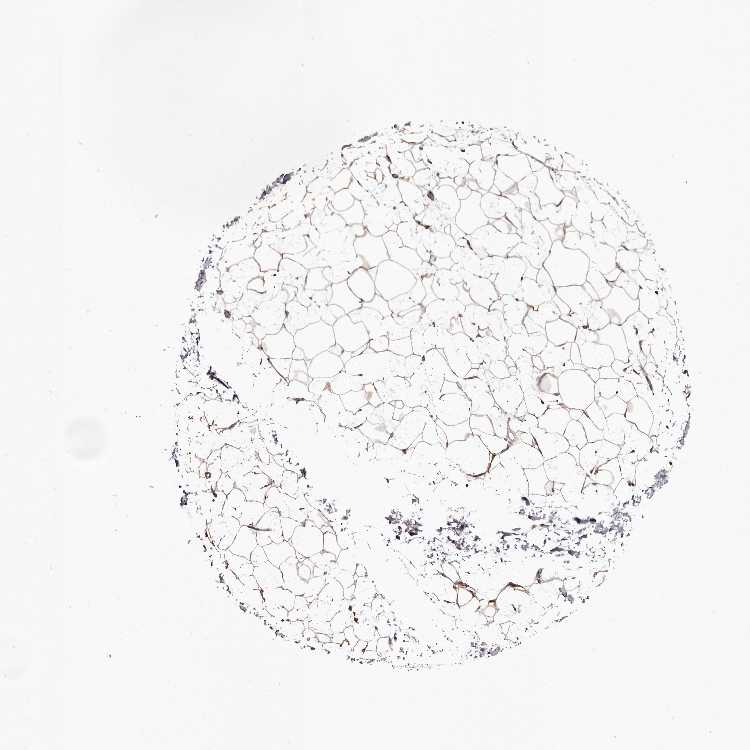

ADIPOSE TISSUE - Antibody stainingi

Antibody staining in the annotated cell types in the current human tissue is reported as not detected, low, medium, or high, based on conventional immunohistochemistry profiling in selected tissues. This score is based on the combination of the staining intensity and fraction of stained cells.

Each image is clickable and will lead to virtual microscopy that enables deeper exploration of all samples and also displays staining intensity scores, fraction scores and subcellular localization as well as patient and tissue information for each sample.

Antibody HPA028427Antibody HPA062167

Adipocytes MediumNot detected